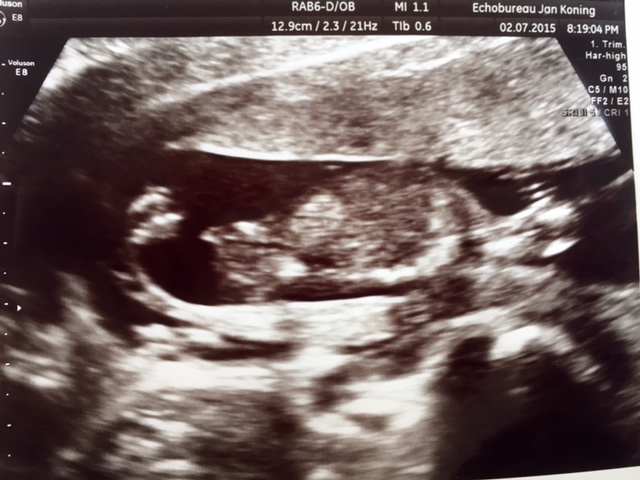

Hi all, I’m very curious. Yesterday we had an ultrasound and we were told we are having a girl yeahhh!!! He gave us this pic and told us that this pic shows te girl parts but I don’t know were to look. Can you help me?

Attachment 25966

This pic is taken yesterday at 15 + 2 weeks ☺️

Not too sure what I'm looking at here. Do you have any other pictures?

Looks girl to me

Sorry, in that case I would say most likely girl xx